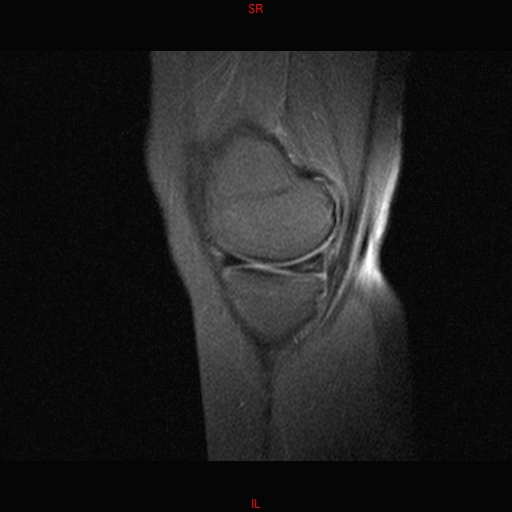

• Resonancia NORMAL RODILLA SAG DENSIDAD PROTONICA